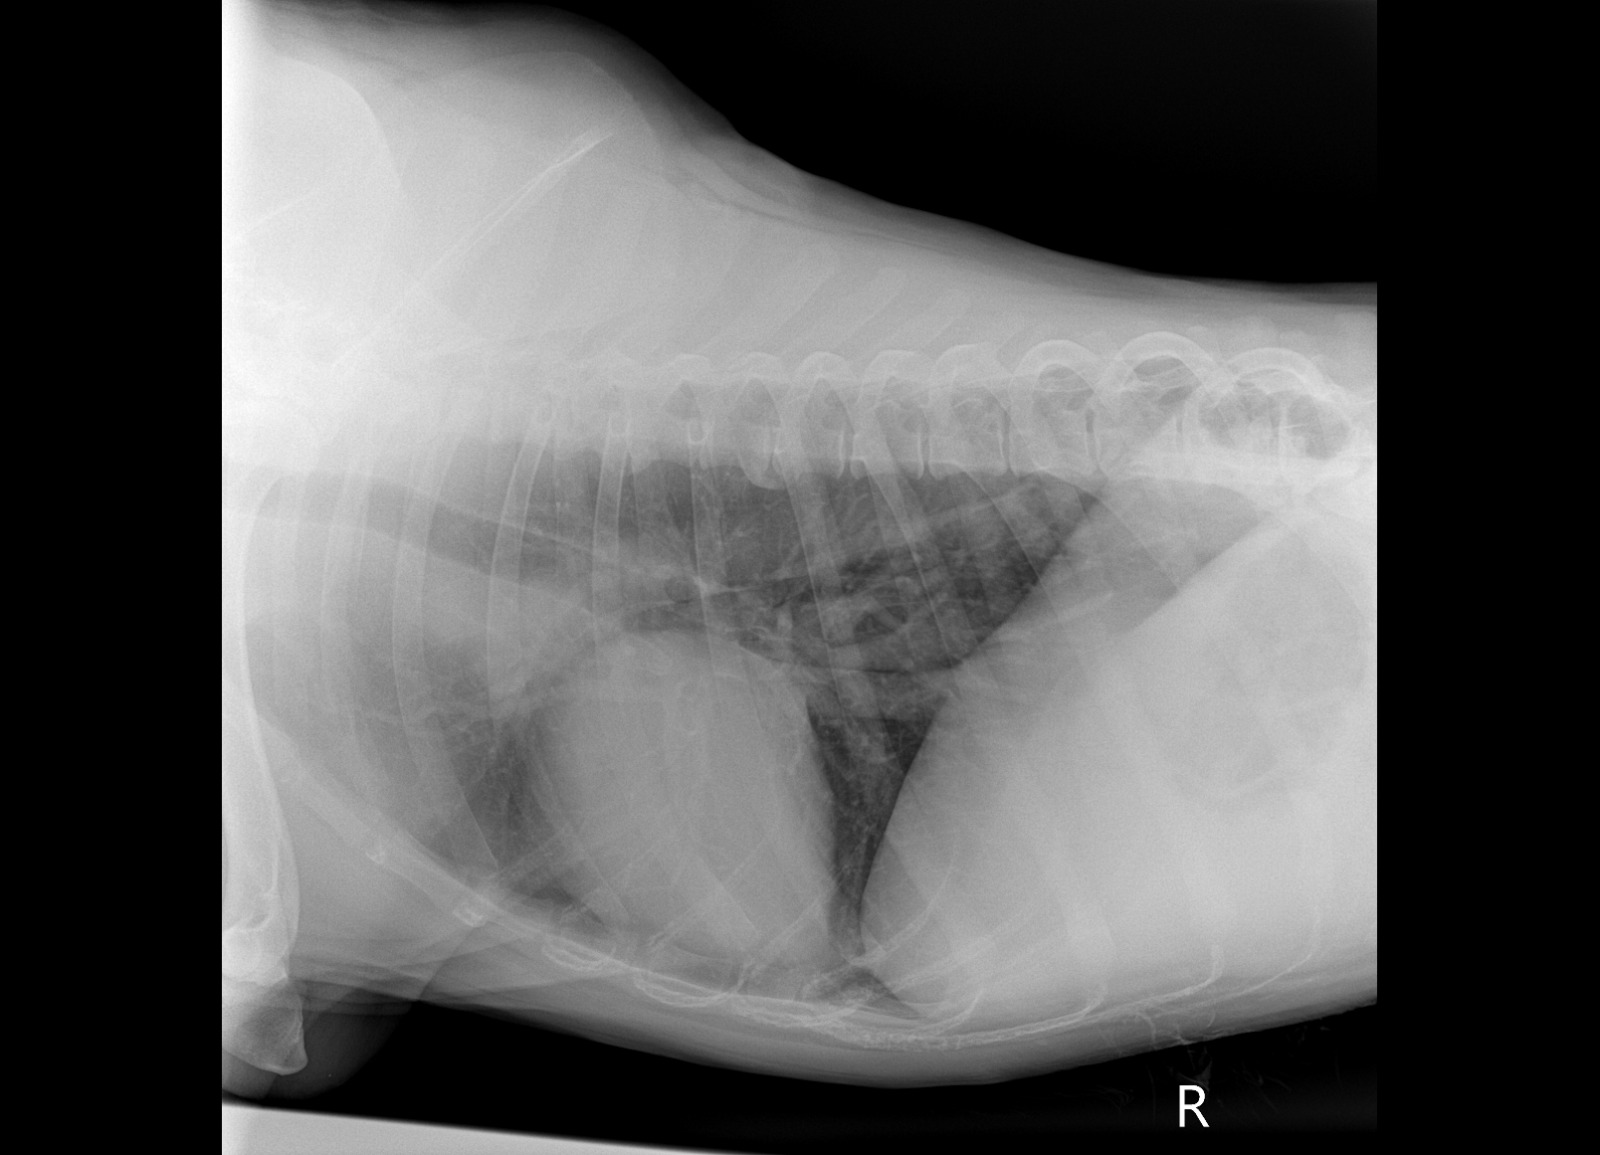

Рентген

Вложения

IMG-20241115-WA0049.jpg

IMG-20241115-WA0050.jpg

IMG-20241115-WA0052.jpg

IMG-20241115-WA0053.jpg

IMG-20241115-WA0051.jpg